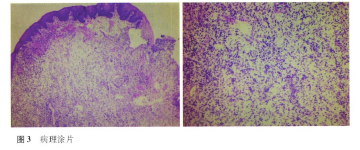

全口根尖片见图2,全口广泛性牙槽骨硬板消失,伴有牙槽骨吸收。血常规检查正常,镜检血细胞形态正常。